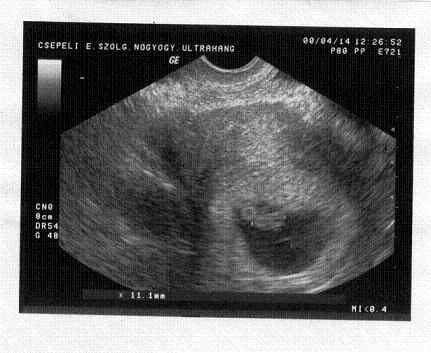

Én ma nekem el kellett menjek a dokihoz mert szombaton megrázott az áram és féltem a csöppömet nehogy baja legyen. De semmi gond vele szép 1.1 centi kis emberke.

Mennem kell EKG-ra meg a körzetihez mert ugyan a babóval minden rendben de velem lehet gond e miatt.

itt a kép.

Kép

harivera